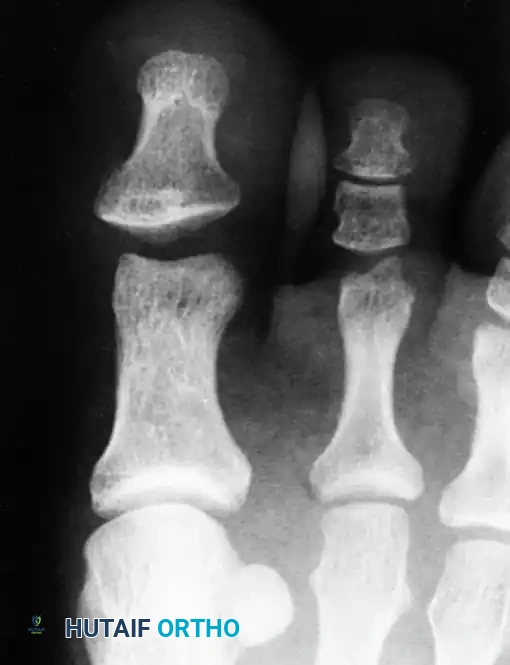

Miki, Yamamuro, and Kitai established a critical radiographic and clinical classification system identifying two distinct types of interphalangeal dislocations of the hallux based on the position of the plantar plate and the degree of deformity.

Type I: The "Deceiving" Dislocation

In a Type I injury, the plantar plate ruptures from one or both of its phalangeal attachments (typically the proximal attachment) and becomes trapped directly within the joint space. Clinically, the gross deformity is minimal, which can be highly deceiving to the evaluating physician. Radiographically, the interphalangeal joint space is markedly widened, but the distal phalanx is not locked in hyperextension.

Fig. 86-49 A, Anteroposterior radiograph shows marked widening of interphalangeal joint. B, Lateral view shows wide joint space; distal phalanx is not hyperextended. (From Miki T, Yamamuro T, Kitai T: An irreducible dislocation of the great toe: report of two cases and review of the literature, Clin Orthop Relat Res 230:200, 1988.)

Type II: The "Locked" Dislocation

The Type II dislocation is more common. The distal phalanx translates completely dorsal to the proximal phalanx, locking the joint in rigid hyperextension. The clinical deformity is obvious and striking. In these cases, the sesamoid bone, embedded within the plantar plate, acts as a mechanical block preventing closed reduction.

Fig. 86-50 Anteroposterior radiograph shows overlapping of proximal phalangeal head and distal phalangeal base. (From Miki T, Yamamuro T, Kitai T: An irreducible dislocation of the great toe: report of two cases and review of the literature, Clin Orthop Relat Res 230:200, 1988.)